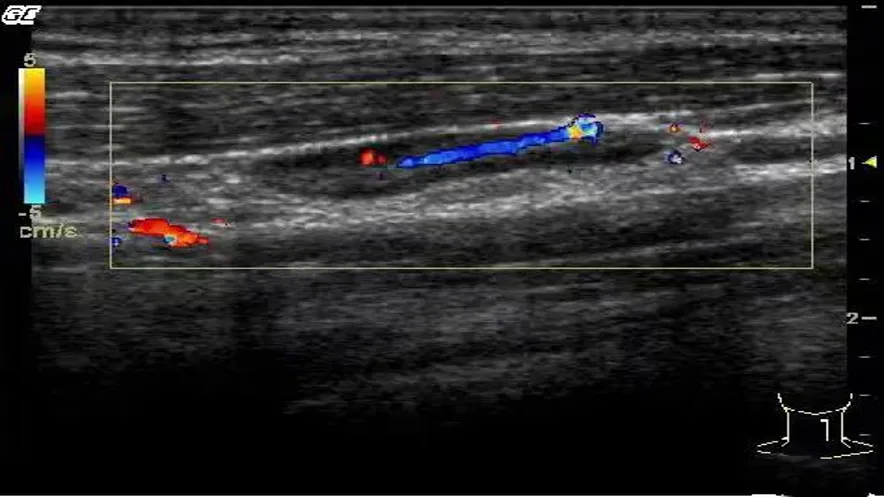

● CDFI检查:门位血流,动脉经淋巴门从髓质向皮质区呈放射状、树杈状、或仅显示髓质内点状或条状血流信号。

脉冲多普勒检测淋巴结内动脉血流为低速低阻型(0.57±0.1)。